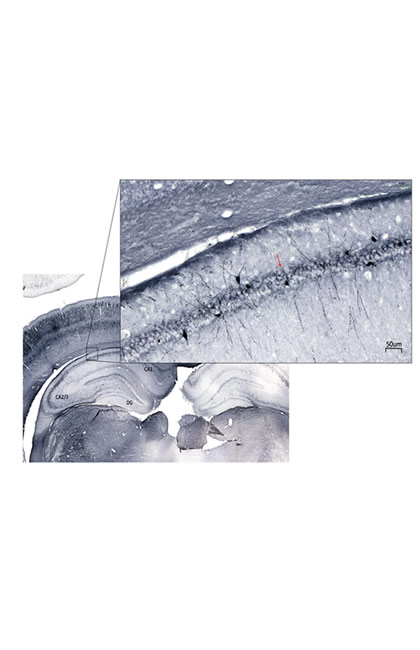

Immuno- histochemistry